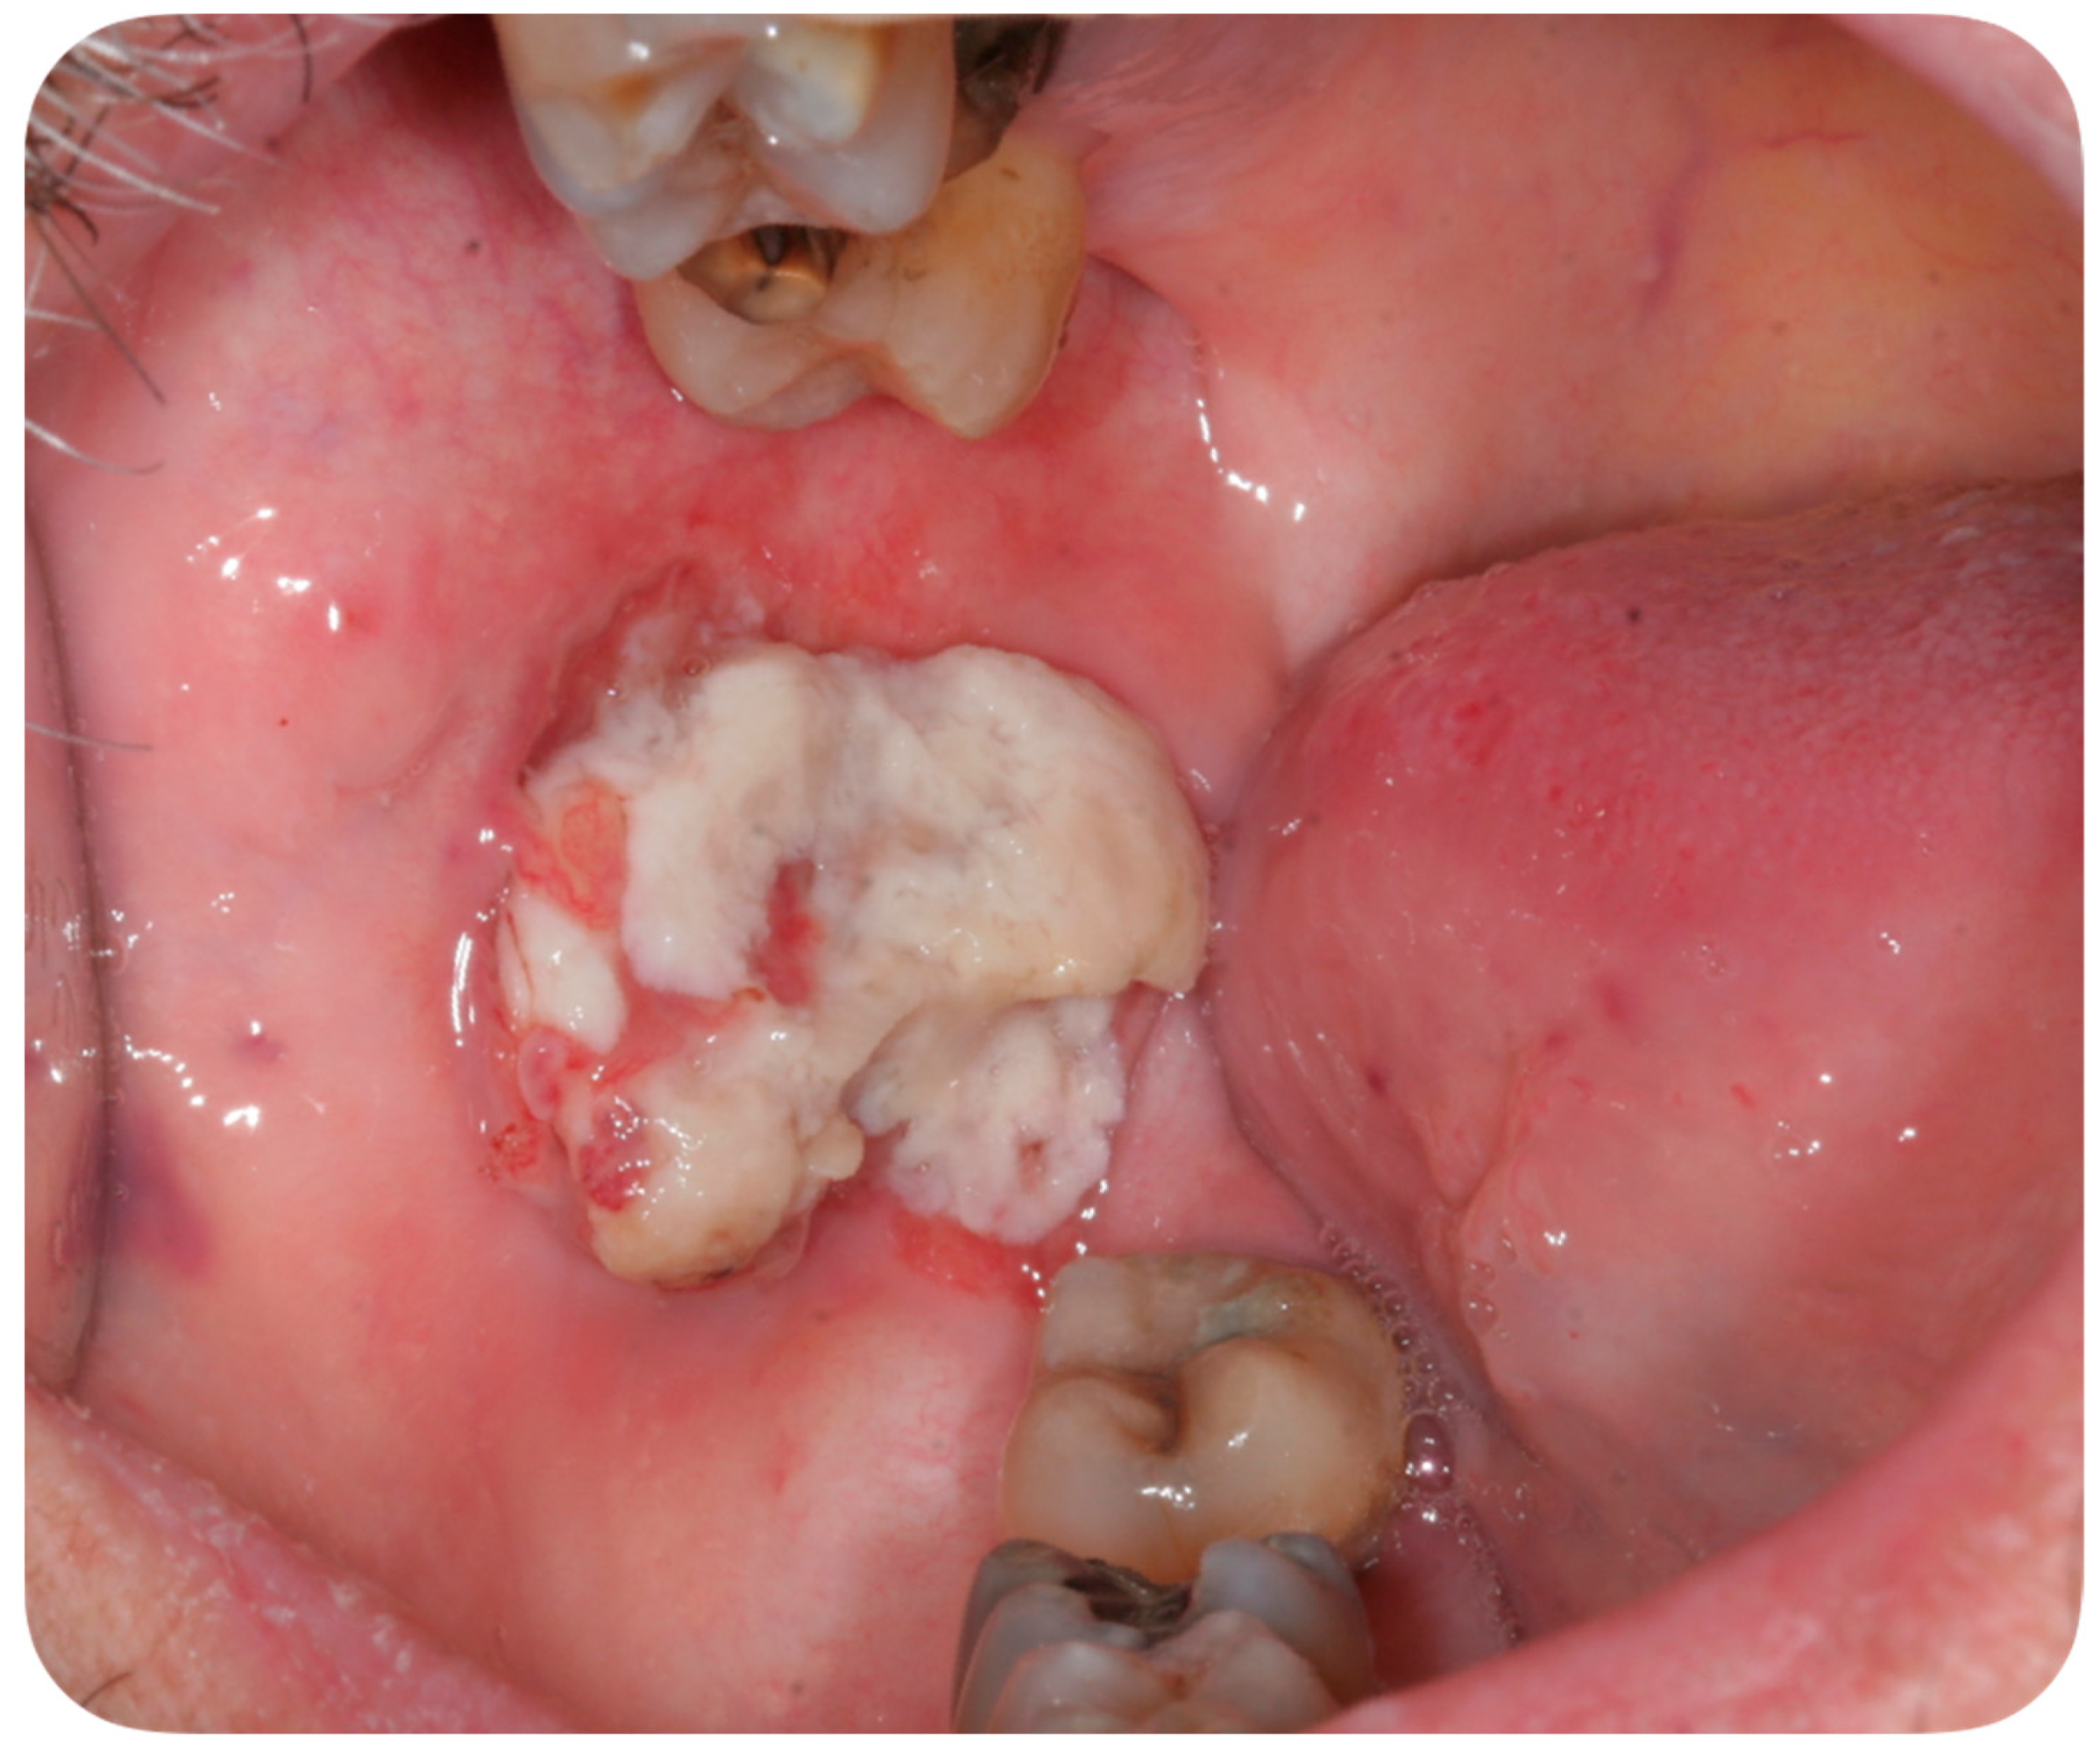

A 56-year-old Caucasian man affected by acute myeloid leukemia (AML) was admitted to the Hematological Department of Policlinico A. Gemelli (Rome, Italy) for febrile neutropenia with multiple oral swellings. The patient’s medical history revealed previous diagnoses of myelodysplastic syndrome (2016), refractory anemia with excess blasts type 1 (RAEB-1), which was treated with ten cycles of decitabine and an allogenic hematopoietic stem cell transplantation. This recurring disease evolved into Acute Myeloid Leukemia (2018). Consequently, re-induction chemotherapy was administered using Chlorambucil and Cytarabine first, followed by a combination of Azacitidine and Venetoclax. In October 2019, the patient was hospitalized for febrile neutropenia with severe thrombocytopenia. At that moment, the patient was receiving antifungal prophylaxis with Posaconazole 300 mg/die. Blood culture was performed and the research for yeasts was negative. The physical examination did not retrieve any skin lesion. The oral examination revealed that three rapidly growing asymptomatic ulcerated swellings, located on both the buccal mucosa and the left mandible, arose 15 days before (Figure 2, Figure 3 and Figure 4).

Figure 3. Asymptomatic ulcerated lesion, located on the left buccal mucosa.

Lesions were light-grayish in color, friable, with a 4 cm diameter, and protruded from the mucosa, interfering with chewing. After a platelet transfusion and local anesthesia (Carbocaine 2% with epinephrine 1:100,000; Dentsply, Verona, Italy), an incisional biopsy was performed together with a microbiological sampling for fungi. The pathology revealed an inflammatory process in association with purulent necrosis and microbial colonies; no granulomas were detected in the specimen. Part of the sample was discharged in liquid Amies medium, then streak-plated on Sabouraud dextrose agar plates supplemented with gentamicin and chloramphenicol (Bio-Rad, Hercules, CA, USA) and BBL CHROMagar Candida plate (BD). We identified species using Bruker Biotyper version MBT 3.1 matrix-assisted laser desorption/ionization time-of-flight (MALDI-TOF) mass spectrometry (Bruker) and nucleotide sequence analysis of the internal transcribed spacer (ITS) regions of the rRNA gene. Microbiological sampling was thus positive for S. clavata, thus the final diagnosis indicated an intraoral fungal infection due to S. clavata. The Minimal inhibitory concentrantions (MICs) of antifungal drugs were determined in parallel according to the European Committee on Antimicrobial Susceptibility Testing (EUCAST) standardized broth microdilution method [27].

This case report describes the first case of oral lesions as the first manifestation of S. clavata infection and the literature review did not find any other case with oral involvement, thus differential diagnosis was particularly demanding. The infection manifested as three rapidly growing asymptomatic ulcerated swellings, located on both the buccal mucosa and the left mandible, that arose 15 days before. Lesions were light grayish in color, friable, with a 4 cm diameter, and protruded from the mucosa, interfering with chewing (Figure 1). Since clinical presentation of common and rare diseases can be really unusual in immunosuppressed patients, the diagnosis of these lesions was particularly challenging, but some clinical characteristics drove the differential diagnosis: rapid growth, ulcerating feature, bilateral onset, and absence of any other symptom (i.e., pain, itching, burning sensation). For these reasons, oral or deep fungal infections, other opportunistic infections, relapses, or new onset of hematological diseases and granulomatous diseases have been considered in the differential diagnosis (Table 3).